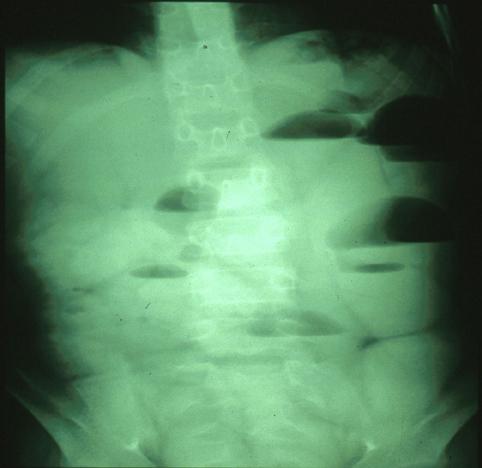

Criteria of Hist.ClassificationMalignant epithelial tumor/Adenocarcinoma

LocationLarge intestine(Colon)/Transverse colon

Technique, MethodX-ray

Macroscopic TypesType 2 Ulcerated type with clear margin/

Size30 - 34

Depth of Tumor Invasionsubserosa (subadventitia)